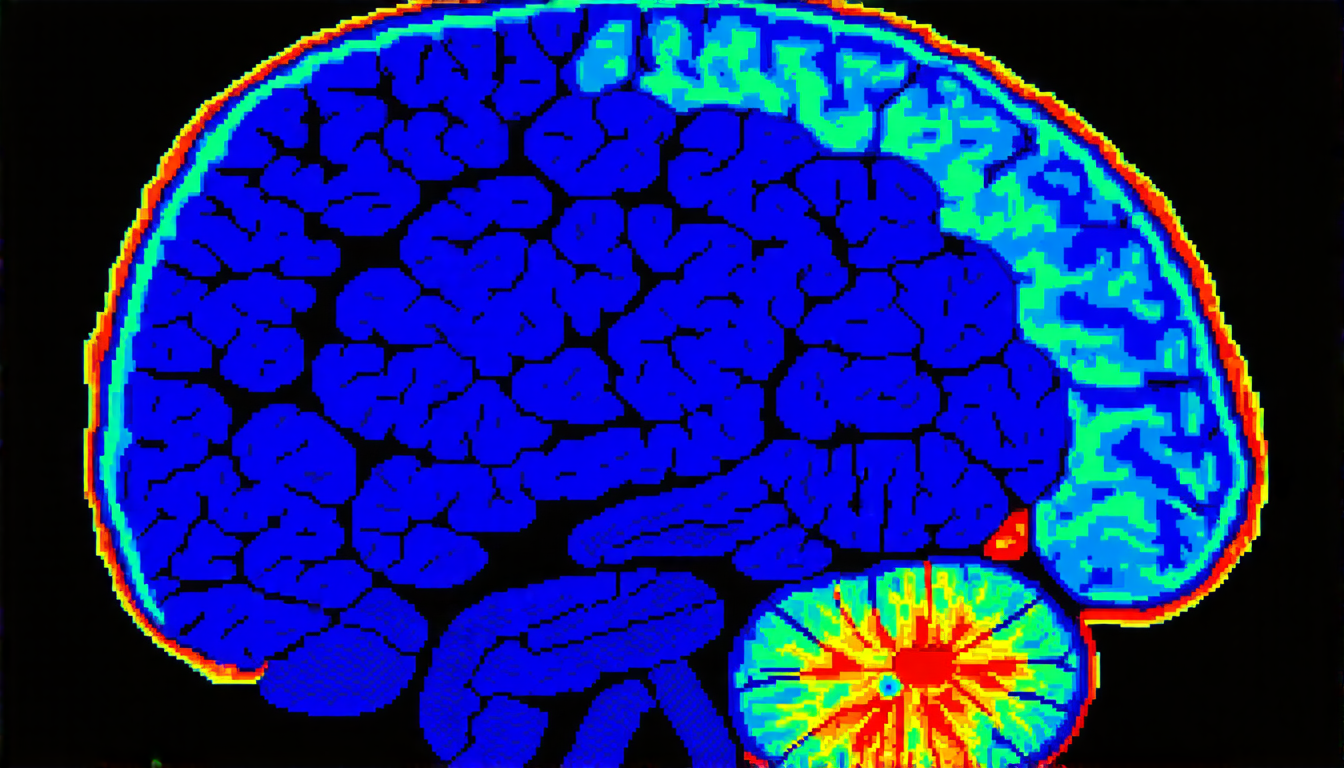

The new approach, however, uses a kinetic model to simulate the behavior of pixels in an image. This model takes into account the interactions between neighboring pixels, allowing for more accurate identification of regions of interest. The researchers have demonstrated the effectiveness of this method on several medical imaging datasets, including MRI and CT scans.

The researchers have also shown that their method can be used for multiple applications, including medical imaging and computer vision. For example, it could be used to segment tumors from healthy tissue in MRI scans or to identify objects within an image.